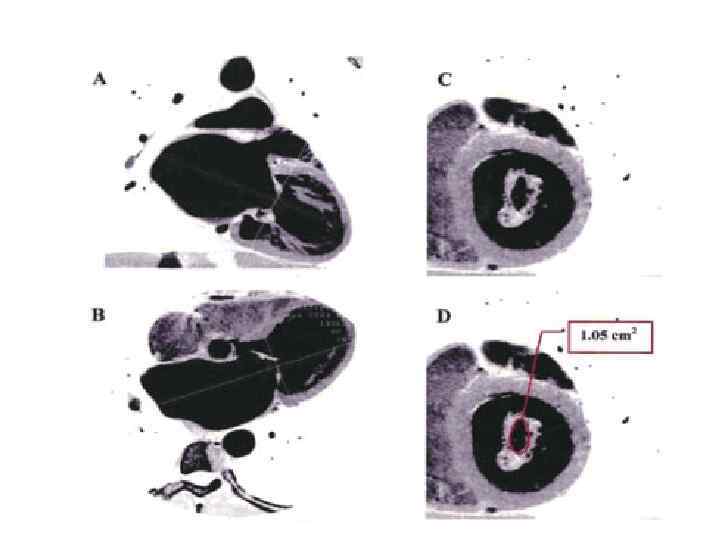

Замена митрального клапана криоконсервантом

Биопротез Митрального Клапана HANCOCK